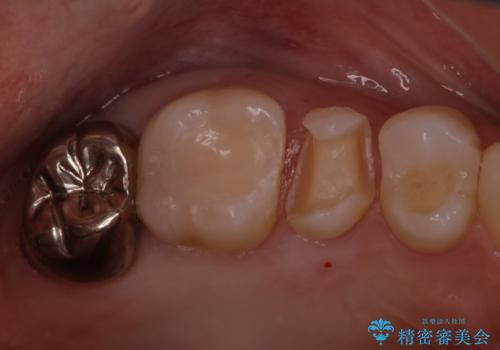

目立つ銀歯をセラミックに変えたい セラミックインレー

- 銀歯が気になるためやり替えたいとのことで来院されました。

セラミックインレーで治療を行いました。

口の中にチラつく銀歯は適合の良いセラミックインレーでやり替えることで綺麗にやり替えることができます。